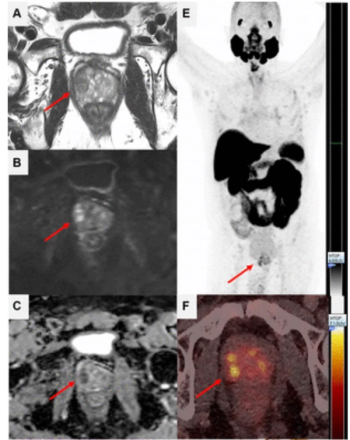

In a cohort of 85 patients with biomechanical recurrence of prostate cancer and PSA values less than 2 ng/mL, positive findings on PET imaging with PSMA-18F DCFPyL led to treatment changes in the majority of patients who had negative findings on conventional imaging, according to new research presented at the SNMMI conference.